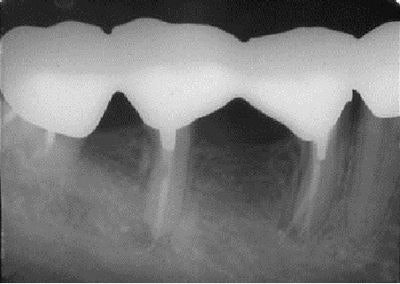

A radiograph taken 4.5 years later shows the completed case with bridge in place, bone fill, and the healed periapical lesion.

There was no need for surgery, and once again the roots served as nature's implants.